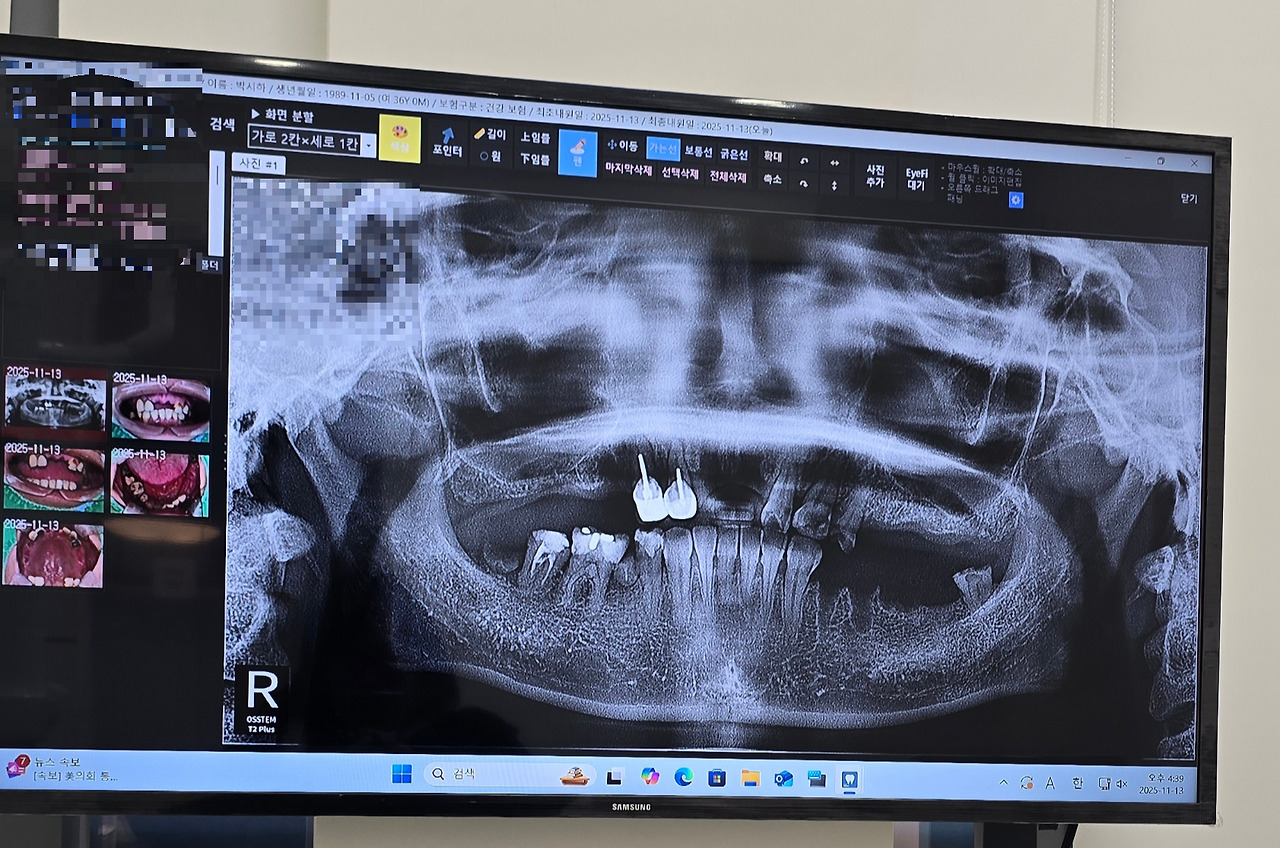

결국 다시 치과를 방문했고 전체 임플란트나 틀니를 생각 중이라 이야기를 드렸다.

솔직히 임플란트를 하려고 3,4곳을 방문했는데 대부분 견적이 1800~3000 정도가 나왔었다.

그리고 문제는 턱이었다. 위, 아래턱이 고르게 앞 뒤가 닫혀야 하는데 어금니 부분이 먼저 닿으면서 앞이 닫혀버리는 구조인지라 임플란트를 하든 틀니를 하던 안쪽부터 깨질 거라고 했다.

이 부분을 해결하기 위해서는 대학병원에 가서 턱 부분 관절을 먼저 수술을 해서 맞춰야 한다 했다.

그리고 다른 치과에서는 다 빼야 한다는 치아들을 그나마 살려보자고 일단 찍어보고 직접 갈아내 보고 나서 발치를 한지 신경치료로 살려볼지 결정하자 하셨다.

그렇게 두어 달 전부터 치료가 시작되었는데.. 역시.. 한 달 넘게 너무 상한치아들을 다 하나하나 발치 하다 보니 위에는 남는 치아가 거의 없었다..